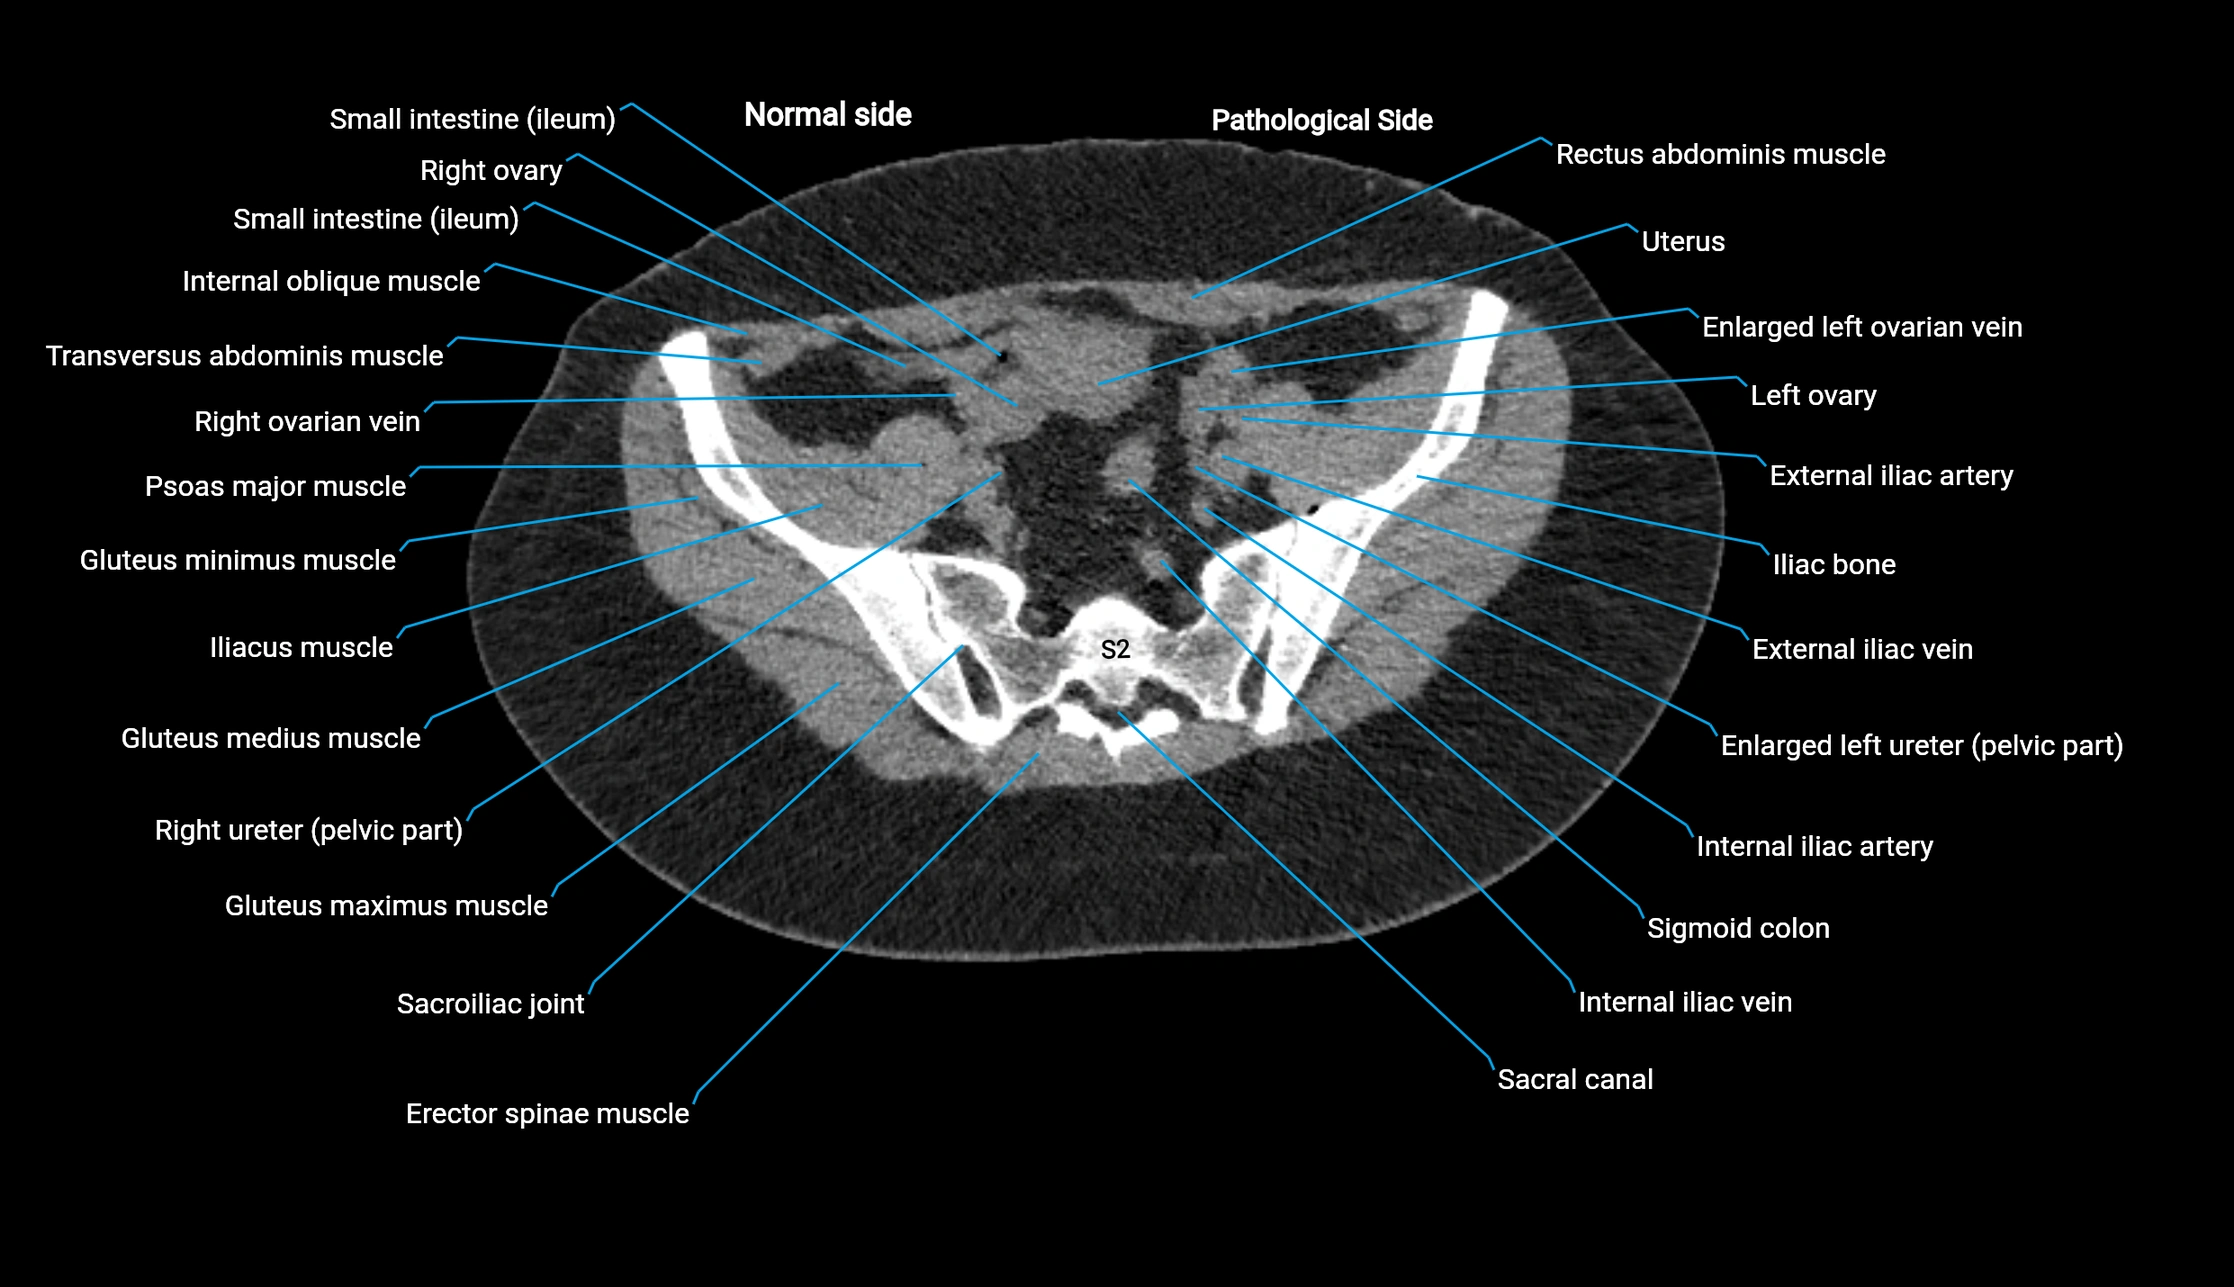

CT image

image